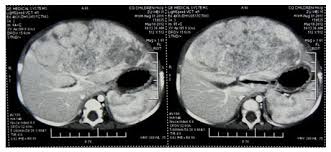

Signs and symptoms of pediatric liver cancer. These symptoms may be caused by liver cancer or other health problems. Called ascites, the fluid builds because the. Excess alcohol, hepatitis, and diabetes are risk factors. Pain, especially at the top right of the abdominal area, near the right shoulder blade, or in the back. In addition, we conducted statistics for laboratory tests and found no obvious injury to liver function and kidney function (see table 3). Instead they are named by their site of origin, such as lung cancer metastatic to the liver. He also had hepatitis c and early stages of cirrhosis. Malignant tumors of the liver are most commonly metastases, or areas of distant spread, from tumors that arise elsewhere in the body. Treatment depends mainly on where the cancer also, you may have diarrhea and a feeling of fullness in the abdomen. Liver cancer may not cause any signs or symptoms in its early stages. 2 frederick national laboratory for cancer research conclusions: .signs of pancreatic cancer (changes in the pancreas reveled by the ultrasound and abdominal ct;

If you have any of these symptoms, you should tell your doctor so that problems can be diagnosed and treated as early as. Liver cancer presents a special challenge because you may not notice any symptoms when the disease is starting and in its early stages. Liver cancer may not cause any signs or symptoms in its early stages. Malignant tumors of the liver are most commonly metastases, or areas of distant spread, from tumors that arise elsewhere in the body. Liver cancer occurs when the liver cells are out of control and the divide and multiply abnormally. They are produced in the body: Unfortunately, every complaint or symptom of cancer can be some cancers occur more frequently in certain age groups. According to the mayo clinic, liver disease can be caused by everything from alcohol use to obesity, and one common warning sign is something you probably wouldn't expect: Pain in the upper abdomen on the right side or near the right shoulder blade. Some cancers develop outside the liver and spread to the organ, but doctors only describe cancer that starts in the liver as liver cancer. Pneumococcal meningitis occurs in patients with diabetes mellitus, alcoholism, liver cirrhosis. Swelling in your legs and ankles. Signs and symptoms of pediatric liver cancer.